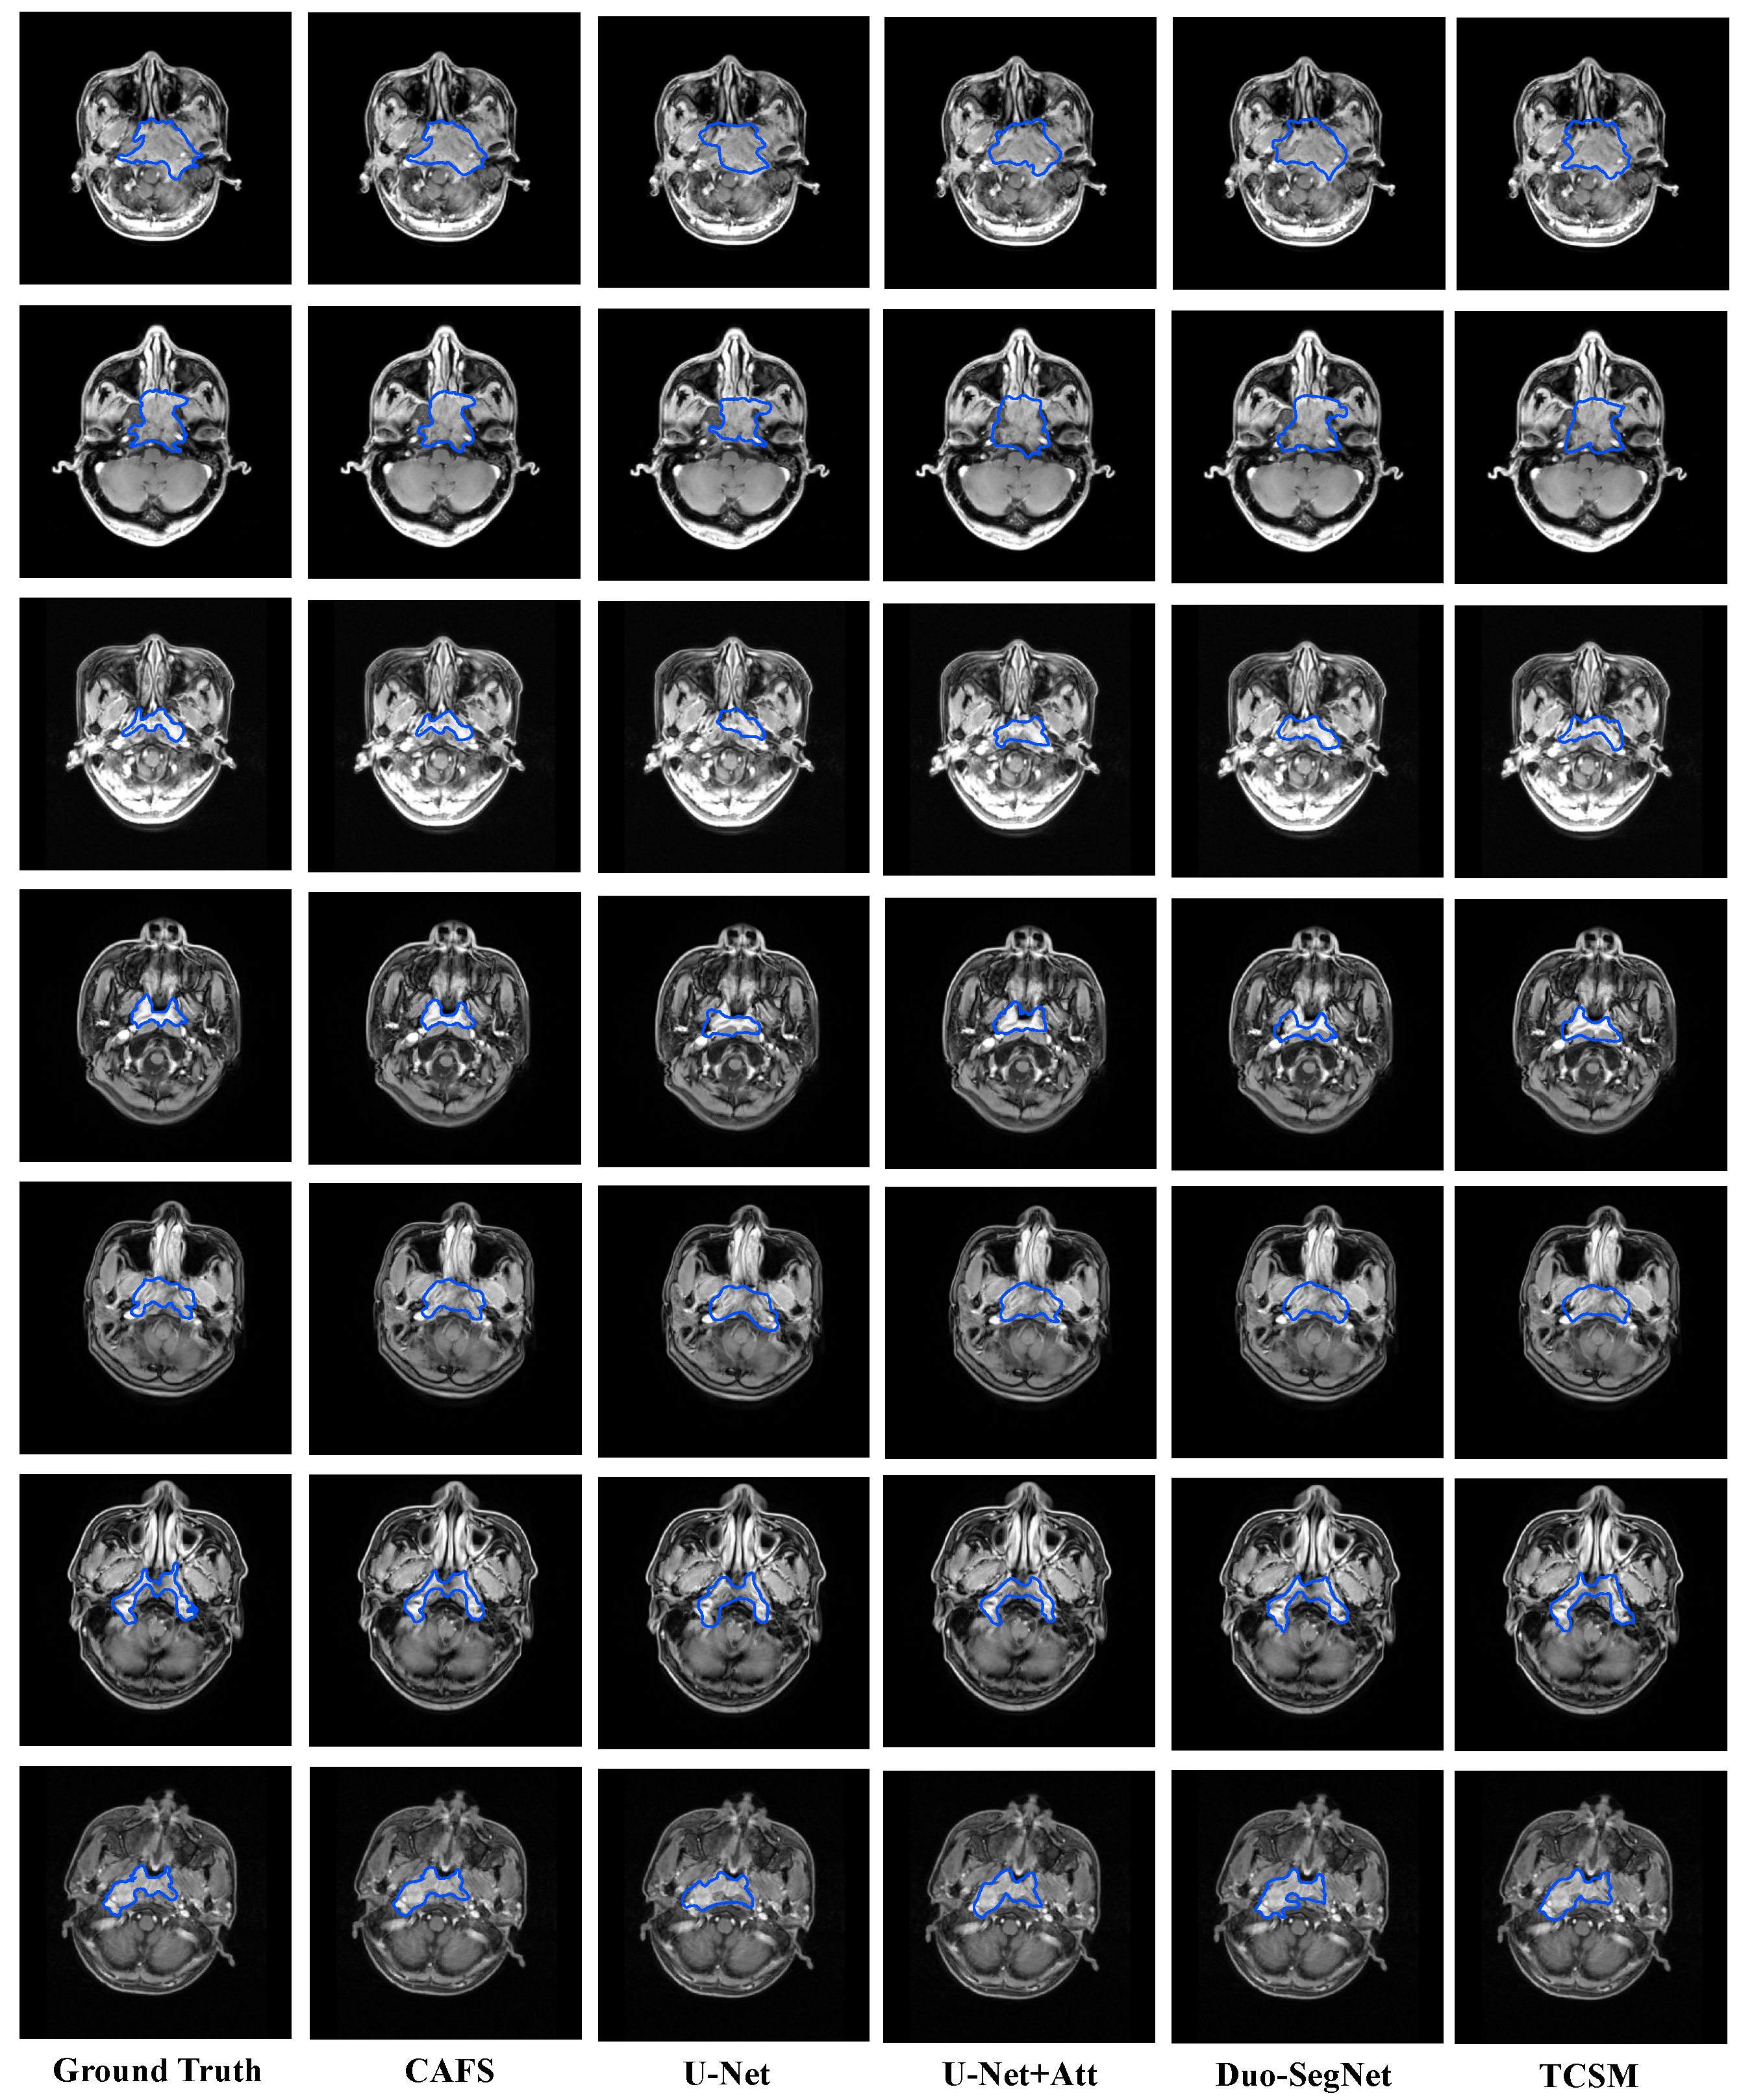

5.3. Comparison with State-of-the-Art Models

| Model | DSC | Jaccard | Precision | Recall |

|---|---|---|---|---|

| CAFS | 0.8723 | 0.7964 | 0.8849 | 0.8796 |

| U-Net [39] | 0.7456 | 0.6868 | 0.6569 | 0.8822 |

| U-Net + Att | 0.8198 | 0.7011 | 0.8202 | 0.8309 |

| Duo-SegNet [66] | 0.8130 | 0.6849 | 0.7966 | 0.8307 |

| TCSM [67] | 0.7970 | 0.6987 | 0.8014 | 0.8978 |